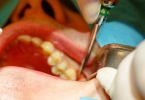

拔智齿通常需要拍片子,通过影像学检查可以明确智齿的生长方向、牙根形态及与邻牙、神经的解剖关系,降低手术风险。口腔全景片或锥形束CT能清晰显示智齿是否阻生、牙根是否弯曲、是否压迫下牙槽神经等重要结构。对于 ...